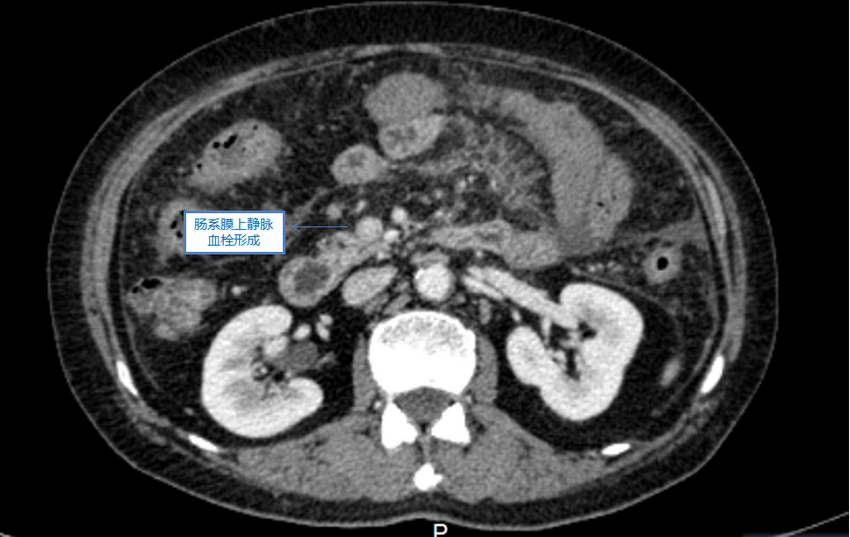

▲ 腹部增强CT提示肠系膜上静脉血栓形成

根据检查结果和丰富的多年临床经验,胃肠甲状腺外科吴万庆副主任医师初步诊断为:肠系膜上静脉血栓形成。他建议进一步行做腹部血管彩超进一步明确病情,结果显示杨奶奶的肠系膜上静脉局部血栓、不全闭塞可能性大,下腔静脉及肠系膜上下动脉血流通畅。通过多方努力,导致患者病痛的罪魁祸首终于找到了!